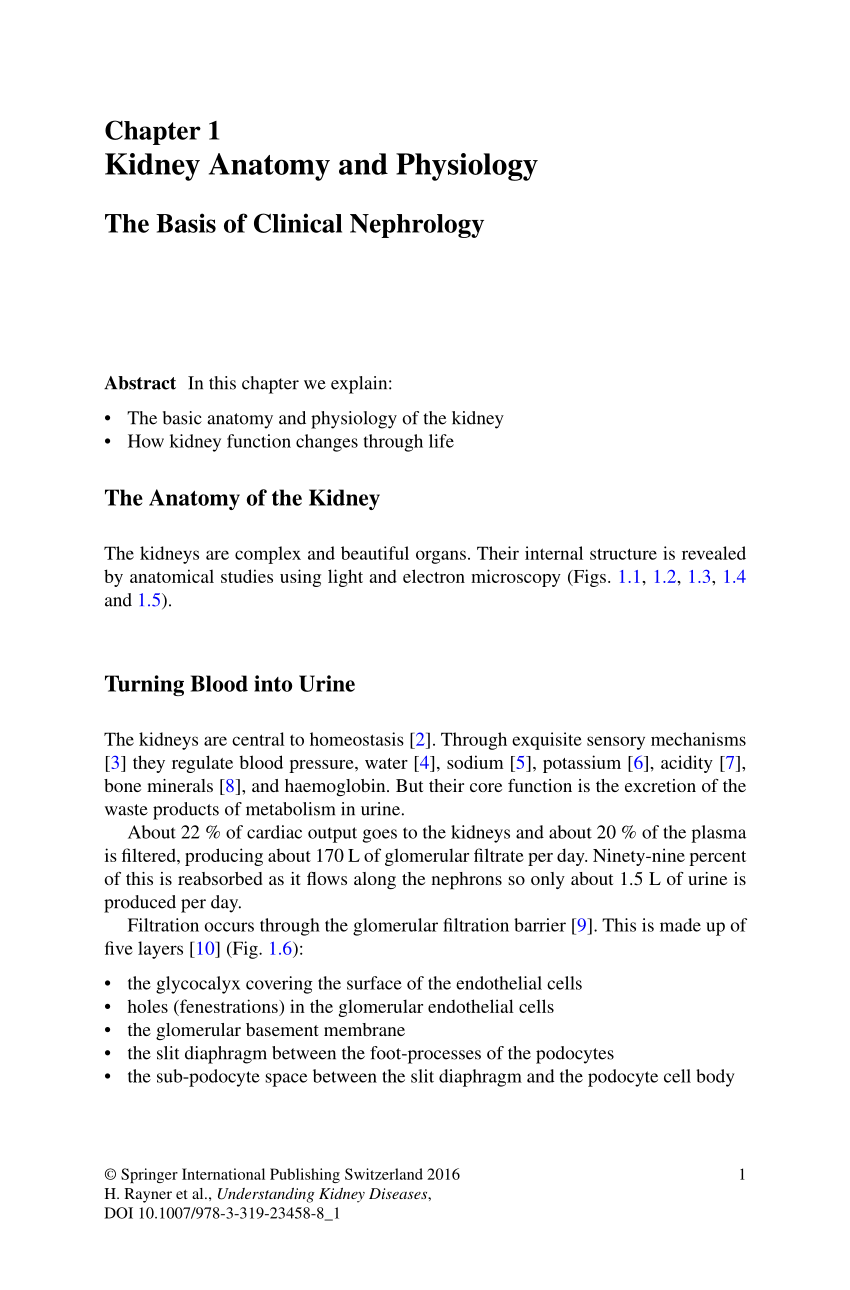

Location of the kidneys there are two kidneys which lie retroperioneally in the lumbar area. The angiotensinconverting enzyme converts angiotensin i to angiotensin ii which stimulates the adrenal cortex to secrete aldosterone a hormone that is involved in increasing blood pressure. The basic anatomy and physiology of the kidney how kidney function changes through life the anatomy of the kidney the kidneys are comple x and beautiful organs.

Pdf Kidney Anatomy And Physiology

Pdf Kidney Anatomy And Physiology